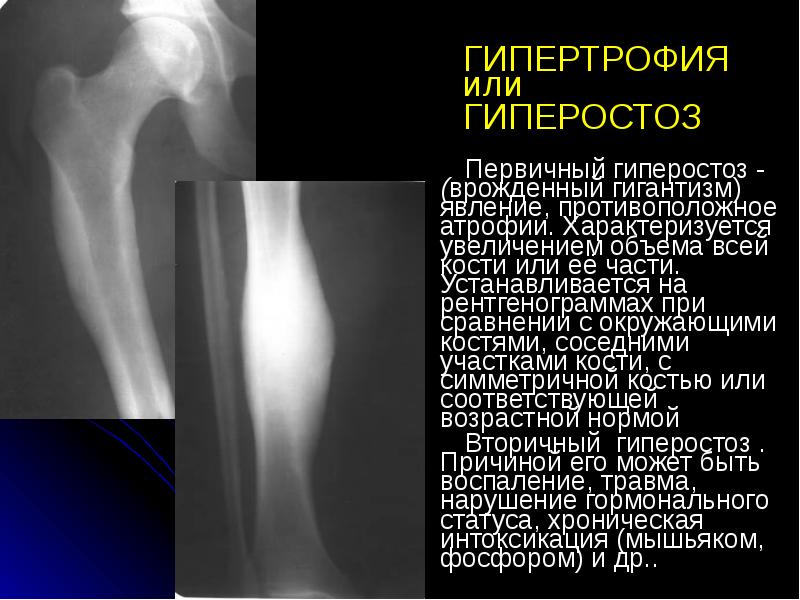

- 25. ГИПЕРТРОФИЯ или ГИПЕРОСТОЗ Первичный гиперостоз - (врожденный гигантизм) явление, противоположное